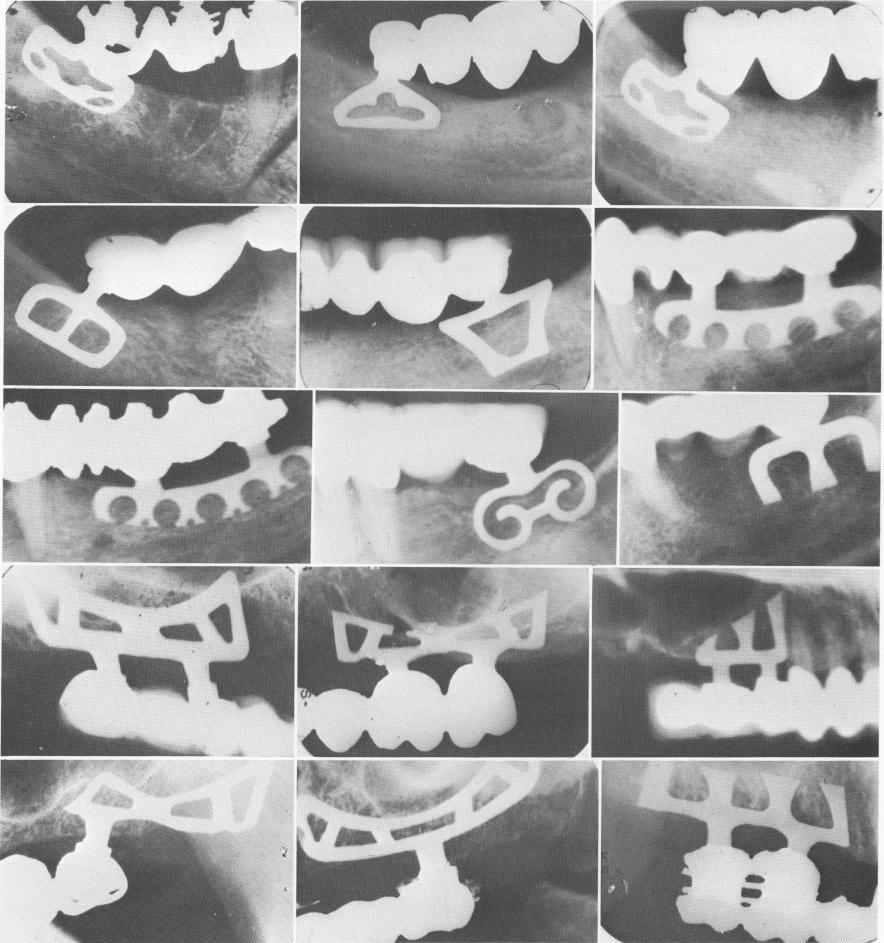

Fig. 11-14. A to I, Blades for free-end saddle areas. J to 0, Blades for maxillary sinus areas.

1 Dental Blade implants for free end saddle areas